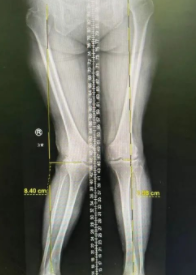

术前

经检查,张大婶被诊断为“双膝关节骨关节病”。由于拖得时间较久,张大婶的右膝外翻已达到25°,这对医生在手术时的矫正力线及软组织平衡方面都提出了更高地要求。

随后,张传开主任、郝亮医生手术团队为其进行了智能导航下右侧人工全膝关节置换术。在智能导航的帮助下,顺利完成截骨及假体安装等操作,使张大婶的下肢力线从术前外翻25°恢复到外翻4°,膝伸直可达0°、膝关节屈曲达至120°,手术很成功。

智能导航下测量畸形角度